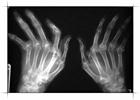

Радиация используется в медицине как в диагностических целях, так и для лечения. Одним из самых распространенных медицинских приборов является рентгеновский аппарат. Получают все более широкое распространение и новые сложные диагностические методы, опирающиеся на использование радиоизотопов. Как ни парадоксально, но одним из основных способов борьбы с раком является лучевая терапия.

Наиболее распространенным видом излучения, применяющимся в диагностических целях, являются рентгеновские лучи. Согласно данным по развитым странам, на каждую 1000 жителей приходится от 300 до 900 обследований в год – и это не считая рентгенологических обследований зубов и массовой флюорографии. Менее полные данные по развивающимся странам показывают, что здесь число проводимых обследований не превышает 100-200 на 1000 жителей. В действительности около 2/3 населения Земли проживает в странах, где среднее число рентгенологических обследований составляет не более 10% от числа обследований в промышленно развитых странах.

Радиоизотопы также используются для исследования различных процессов, протекающих в организме, и для локализации опухолей. За последние 30 лет их применение сильно возросло, и все же они и сейчас применяются реже, чем рентгенологические обследования. Информация об использовании радиоизотопов довольно ограниченна, но имеющиеся данные позволяют предположить, что в промышленно развитых странах на 1000 жителей приходится лишь 10-40 обследований. Так же трудно оценить и дозы; результаты одного исследования, проведенного в Японии, показывают, что годовая эффективная эквивалентная доза составляет ~20 мкЗв на человека. Коллективные эффективные эквивалентные дозы лежат в диапазоне от 20 чел-Зв на 1 млн. жителей в Австралии до ~150 чел-Зв в США.